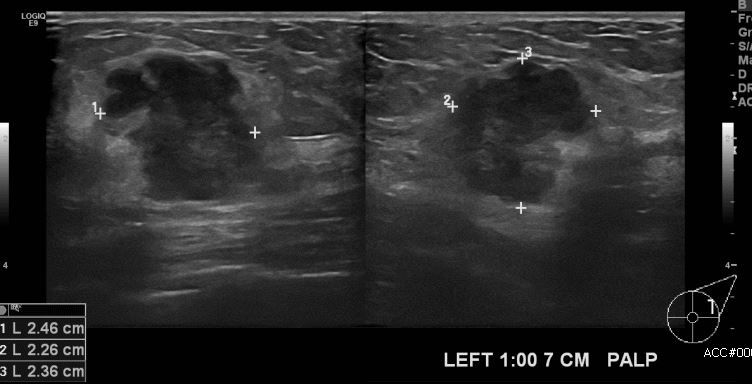

좌측 만져지는 멍우리로 내원하신 50대 여성 분으로 좌측 1시 방향에서 7cm 떨어진

거리의 만져지는 혹 중앙핵생검 시행하여 좌측 침윤성 유관암 진단 되었습니다.